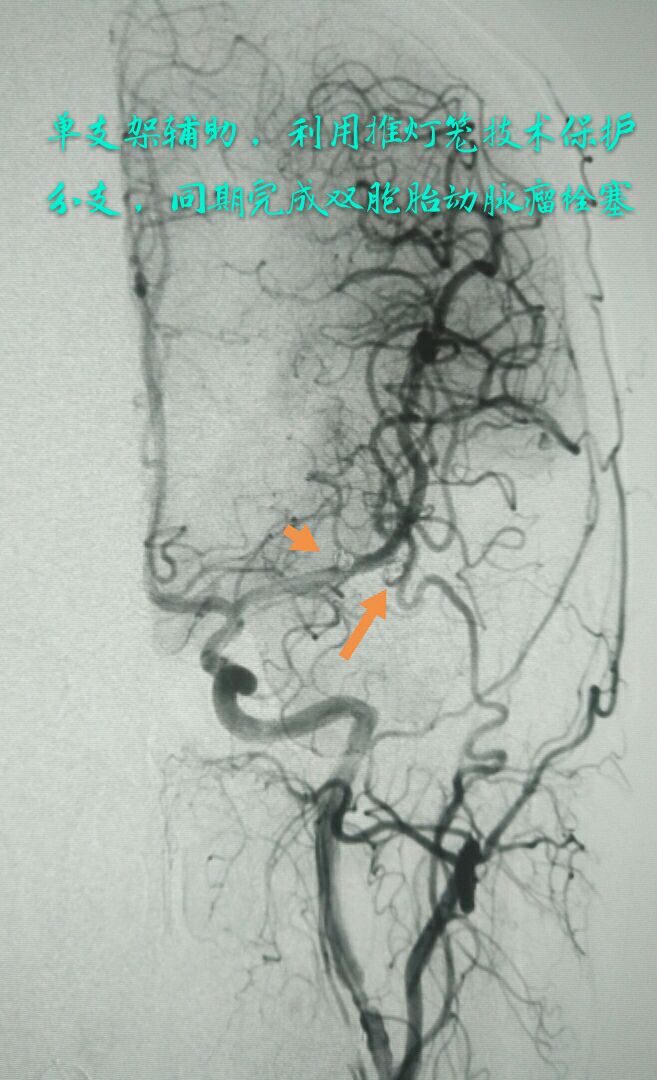

病例五:中年女性患者,2年前因脑梗塞导致一侧肢体不完全性瘫痪,近一年间断性头痛,DSA示左侧大脑中动脉双胞胎动脉瘤,载瘤动脉纤细,瘤颈部累及重要分支

难点:载瘤动脉保护容易,但瘤颈部分支纤细,无法释放支架,保护困难,最终采用单支架半释放、推灯笼技术栓塞远端动脉瘤,全释放并推灯笼技术栓塞近段动脉瘤,瘤颈部分支得到充分保护